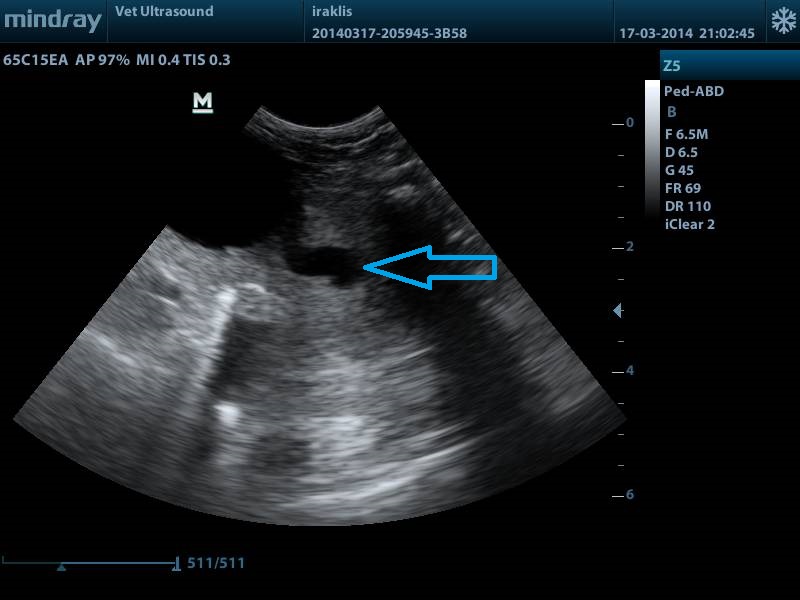

ΤΟ ΒΕΛΟΣ ΔΕΙΧΝΕΙ ΤΟΝ ΛΙΘΟ Ο ΟΠΟΙΟΣ ΒΡΙΣΚΕΤΑΙ ΣΤΗΝ ΟΥΡΟΔΟΧΟ ΚΥΣΤΗ ΚΑΙ ΛΟΓΩ ΤΗΣ ΣΤΑΣΗΣ ΤΟΥ ΑΣΘΕΝΗ ( ΟΡΘΙΑ ΘΕΣΗ) ΕΧΕΙ ΠΕΣΕΙ ΣΤΗΝ ΕΝΔΟΠΡΟΣΤΑΤΙΚΗ ΜΟΙΡΑ ΤΗΣ ΟΥΡΗΘΡΑΣ. ΧΑΡΑΚΤΗΡΙΣΤΙΚΗ ΕΙΝΑΙ Η ΣΚΙΑ Η ΟΠΟΙΑ ΦΑΙΝΕΤΑΙ ΚΑΤΩ ΑΠΟ ΤΟΝ ΛΙΘΟ ΛΟΓΩΣ ΤΗΣ ΕΝΤΟΝΗΣ ΑΠΟΡΡΟΦΗΣΗΣ ΤΟΥ ΗΧΟΥ. ΤΑ ΑΣΤΕΡΙΑ ΑΦΟΡΙΖΟΥΝ ΤΟΝ ΕΝΑΝ ΛΟΒΟ ΤΟΥ ΠΡΟΣΤΑΤΗ ΣΕ ΕΠΙΜΗΚΗ ΤΟΜΗ, Ο ΟΠΟΙΟΣ ΕΧΕΙ ΜΙΚΡΕΣ ΚΥΣΤΕΙΣ ΣΤΟ ΠΑΡΕΓΧΥΜΑ ΤΟΥ.